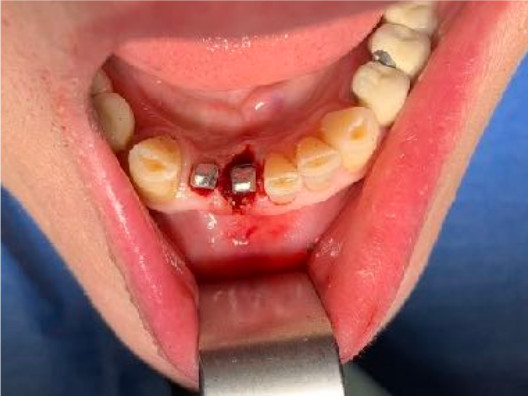

N.impianti inseriti

1

Zona dentale

41

Immediato in leggera occlusione

Complicanze

nessuna